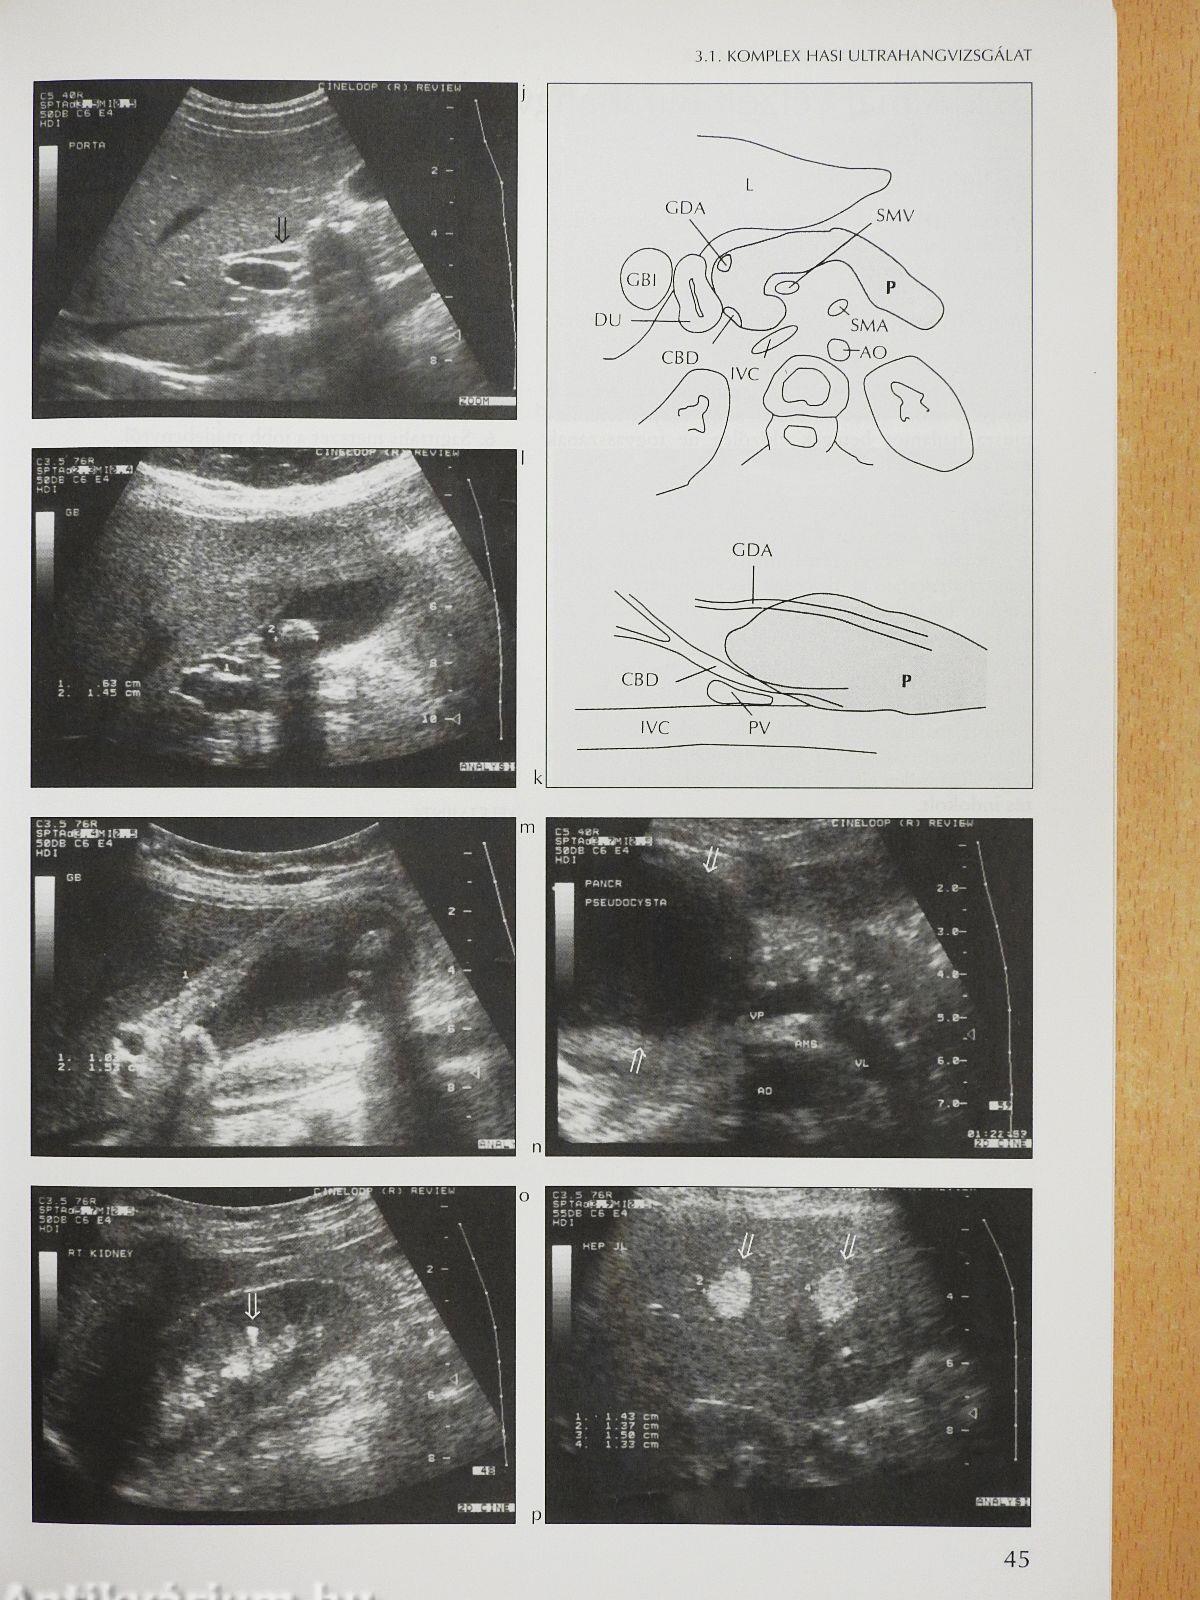

Megjegyzés: Harkányi Zoltán szerkesztő által dedikált példány. Fekete-fehér fotókkal, ábrákkal illusztrálva.

Komplex hasi ultrahangvizsgálat42